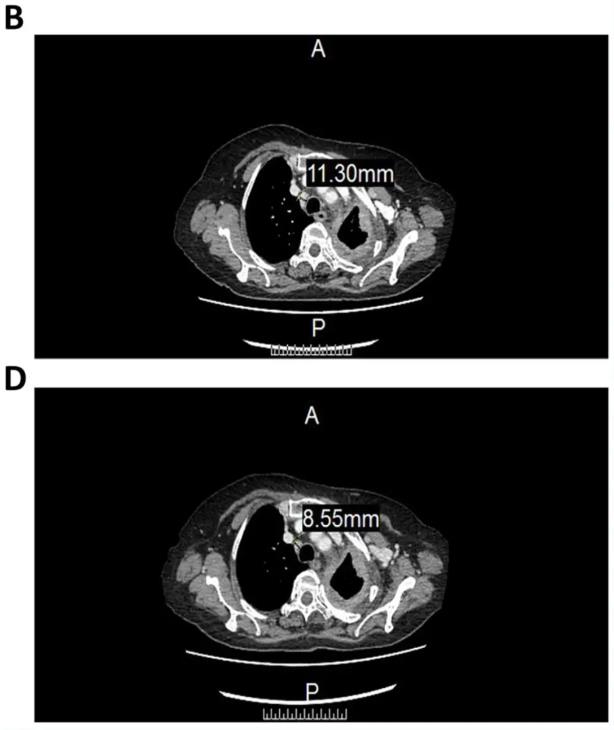

幸运的是,该患者在入组经过3个周期的CCCR-NK92细胞治疗后,影像学(CT)评估显示,CCCR-NK92细胞起到了一定的抗肿瘤效果,具体结果如下:

1、患者气管前-后腔静脉间质区的淋巴结,从11.3毫米(mm),缩小至8.55mm(详见下图)。

▲图源“Sage Journals”,版权归原作者所有,如无意中侵犯了知识产权,请联系我们删除